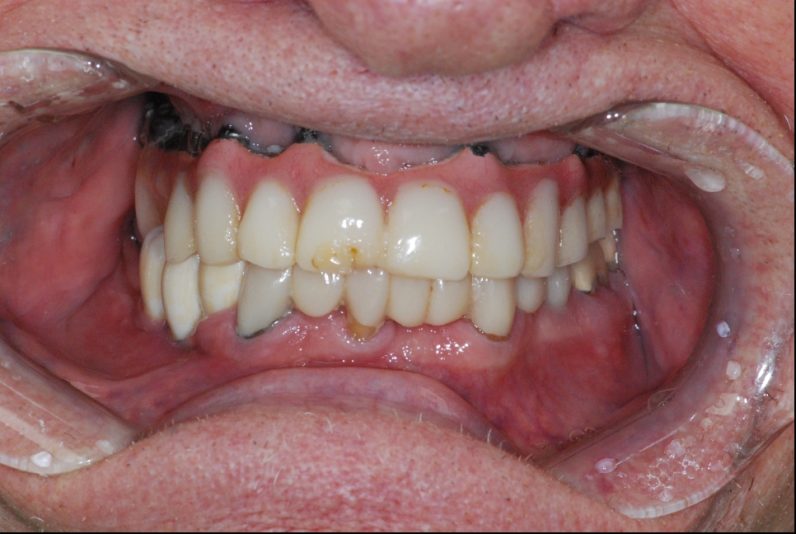

Hey, I will be removing this hybrid denture for replacement. I am having a difficult time locating the access screws for removal. Can anyone please help me find them? Implants are placed at site 3,5,7,9,12,13,15. Thank you for your help!

It is always a bit tedious and a pain but typically using various X-rays and especially a pano can give you areas to try to access slowing until you find all the screws, slow and patience is keep to not over prep into the screws

Use air and really dry the acrylic but you can see the outline of the access on the occlusal of 5,6. I would block enough time and just go slow. Best part is since the prosthesis is plastic it’s easily repairable. U got this.